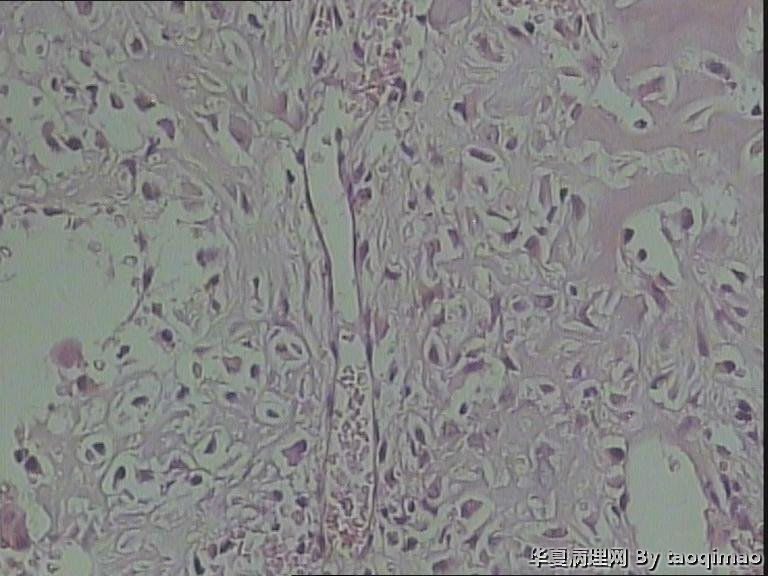

• 肋骨肿物,求助图3

图3

患者女,31岁,胸部CT第八肋骨肿瘤,肿物在肋骨内突出骨外膜,大小2.3X1.5.切面灰白质韧

这是一部分容易取下来的肿瘤,其余部分还在脱钙中

骨母细胞瘤。矿化不均要除外骨母细胞型骨肉瘤,虽然肿块小了点。还是找找核分裂,看看X线的好。

那就是骨样骨瘤。